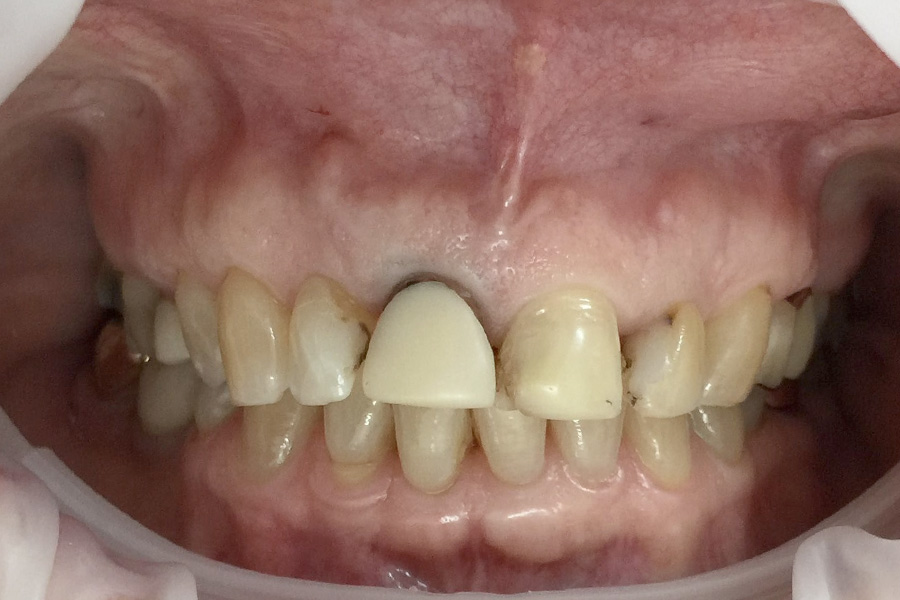

Christine had a crown on a root canal treated upper right central incisor that had a receding gum line.

Some of the white fillings on other front teeth were also stained. Pauline decided to have the crown replaced and ceramic veneers placed on other three adjacent teeth. The new crown is all ceramic and blends in more naturally with the veneers.